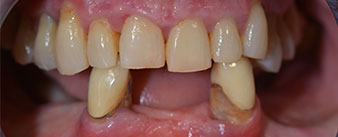

La paciente de 64 años se presentó con una dentición residual compuesta por las piezas dentales 38, 33 y 43 en el maxilar inferior y con una prótesis temporal fijada con ganchos en el maxilar inferior (figs. 1 y 2).

El tratamiento periodóntico necesario y la extracción de las piezas en el maxilar superior debía realizarse en un momento posterior, ya que la paciente es profesora y, en el momento de la consulta, estaba ocupada con los exámenes para las pruebas de acceso a la universidad. La paciente no podía comer ni hablar adecuadamente, ya que la prótesis temporal se rompía con mucha frecuencia y con una carga mínima.

Tras explicarle las distintas opciones de tratamiento, la paciente se decidió por la extracción de la dentición residual en el maxilar inferior, la implantación inmediata y el tratamiento con el método Fast & Fixed (bredent medical), con el que la prótesis dental fijada provisionalmente se atornilla sobre cuatro implantes en el mismo día de la intervención. El objetivo era operar a la paciente el viernes para que el lunes pudiera tomar parte en los exámenes orales para la prueba de acceso a la universidad.